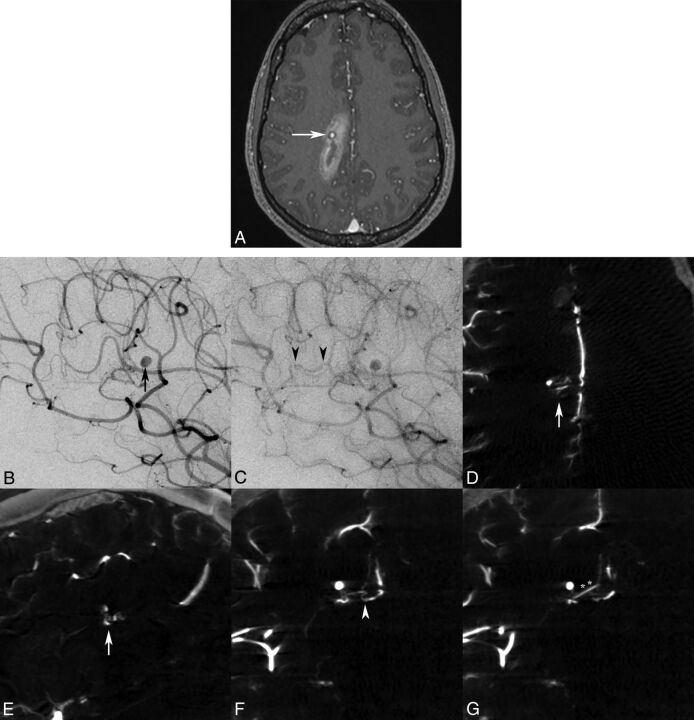

A 21-year-old woman presented to our institution with sudden headache and dizziness for 1 hour. Initial CT/CTA and MR imaging/MRA brain studies revealed an acute paramedian right frontoparietal intracerebral hemorrhage and a distal pericallosal aneurysm with suspicion of an underlying occult vascular malformation, but no abnormal vascular flow voids or nidus was seen (Fig 2A). Subsequent DSA with the 3DRA/IA-CBCTA technique was performed 2 days later confirming a 2-mm pericallosal-splenial artery aneurysm/pseudoaneurysm with suggestion of an early draining vein (Fig 2B, C), but a definitive arterial feeder and <5-mm nidus were only visualized on IA-CBCTA multiplanar reconstructions to confirm the diagnosis of a micro-AVM (Fig 2D–G).

Fig 2.

Axial MR imaging MPRAGE postgadolinium (A) image demonstrates a right parasagittal frontoparietal intraparenchymal hemorrhage with a contrast-enhancing pseudoaneurysm (white arrow), consistent with the rupture site. Lateral oblique DSA images in the early arterial phase confirm a pericallosal anterior cerebral artery aneurysm/pseudoaneurysm (B, black arrow), with a subtle early draining vein in the capillary phase (C, black arrowheads), but no distinct vascular nidus was identified by either observer. Only IA-CBCTA multiplanar reconstructions clearly delineate a <5-mm micronidus on axial and sagittal reconstructions (D and E, white arrows). Coronal multiplanar reconstructions also assist in identification of the small arterial feeder from the pericallosal-splenial artery branch (F, white arrowhead) and single draining vein (G, double asterisks) directly associated with the micronidus and flow-induced pseudoaneurysm.